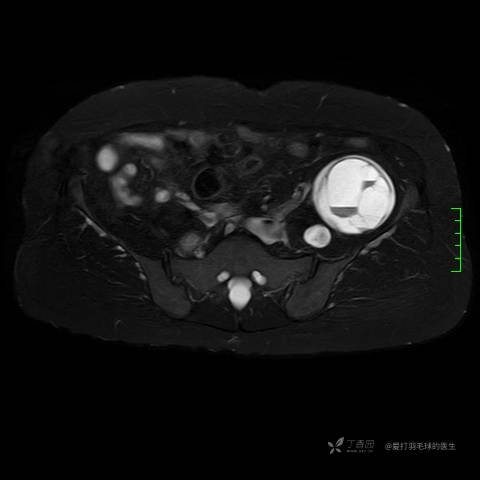

主诉:患者因反复右侧腰痛伴右下肢麻木2年余入院。

简要病史:自诉右甲状腺功能亢进症多年,规律服药,平素多有心悸、胸闷、活动后明显。既往腰椎椎管内肿瘤切除术。